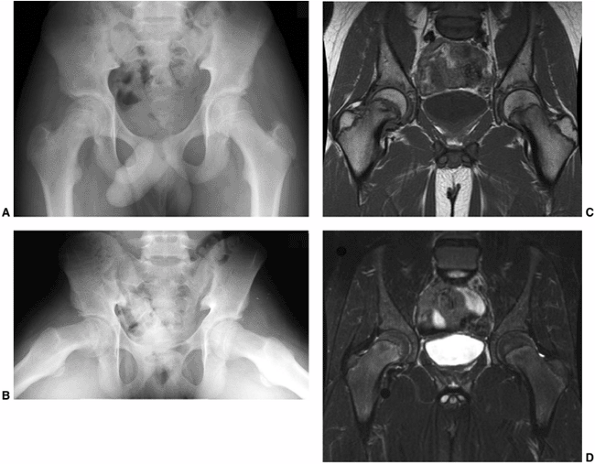

![]() |

Figure 26.1

Radiographs of a 12-year-old boy with 3 months of hip pain show typical findings of a slipped capital femoral epiphysis (SCFE). A: Anteroposterior view demonstrates physeal widening, osteopenia, decreased epiphyseal height, increased metaphyseal-teardrop distance, and asymmetry of Klein’s line. B: Although many of these features are seen on the anteroposterior view, the most striking feature is how much more easily the displacement is seen on the frog lateral view. The importance of obtaining lateral views when evaluating for SCFE cannot be overemphasized. |

Figure 26.2

A 12-year-old boy presented with pain in the right hip for two months. On further questioning, he reported some vague, intermittent symptoms in the left hip. Physical examination revealed pain in the right hip and obligate external rotation, but no such findings on the left. A, B: Anteroposterior and frog pelvis views at the time of presentation. A right slipped capital femoral epiphysis (SCFE) is evident, without definite plain radiographic changes on the left. C, D: Because of the vague left hip symptoms, magnetic resonance imaging (MRI) was done to rule out a left SCFE. MRI demonstrated physeal widening and irregularity (T1: flip angle 90, TR 700, TE 18) (seen best in C) and signal change on the right, mostly in the metaphysis in this case (fat saturation: flip angle 90, TR 4500, TE 75.37) (best seen in D), without any definite abnormalities on the left. Only the right hip underwent in situ fixation because of the normal physical examination and the lack of considerable MRI findings in the left hip. The patient denied ongoing pain in the left hip until nine months following in situ pinning of the right hip. He then had progressive pain in the left hip and re-presented to the orthopaedist one month later, at which time a mild left SCFE was noted and in situ fixation of the left hip was performed. |